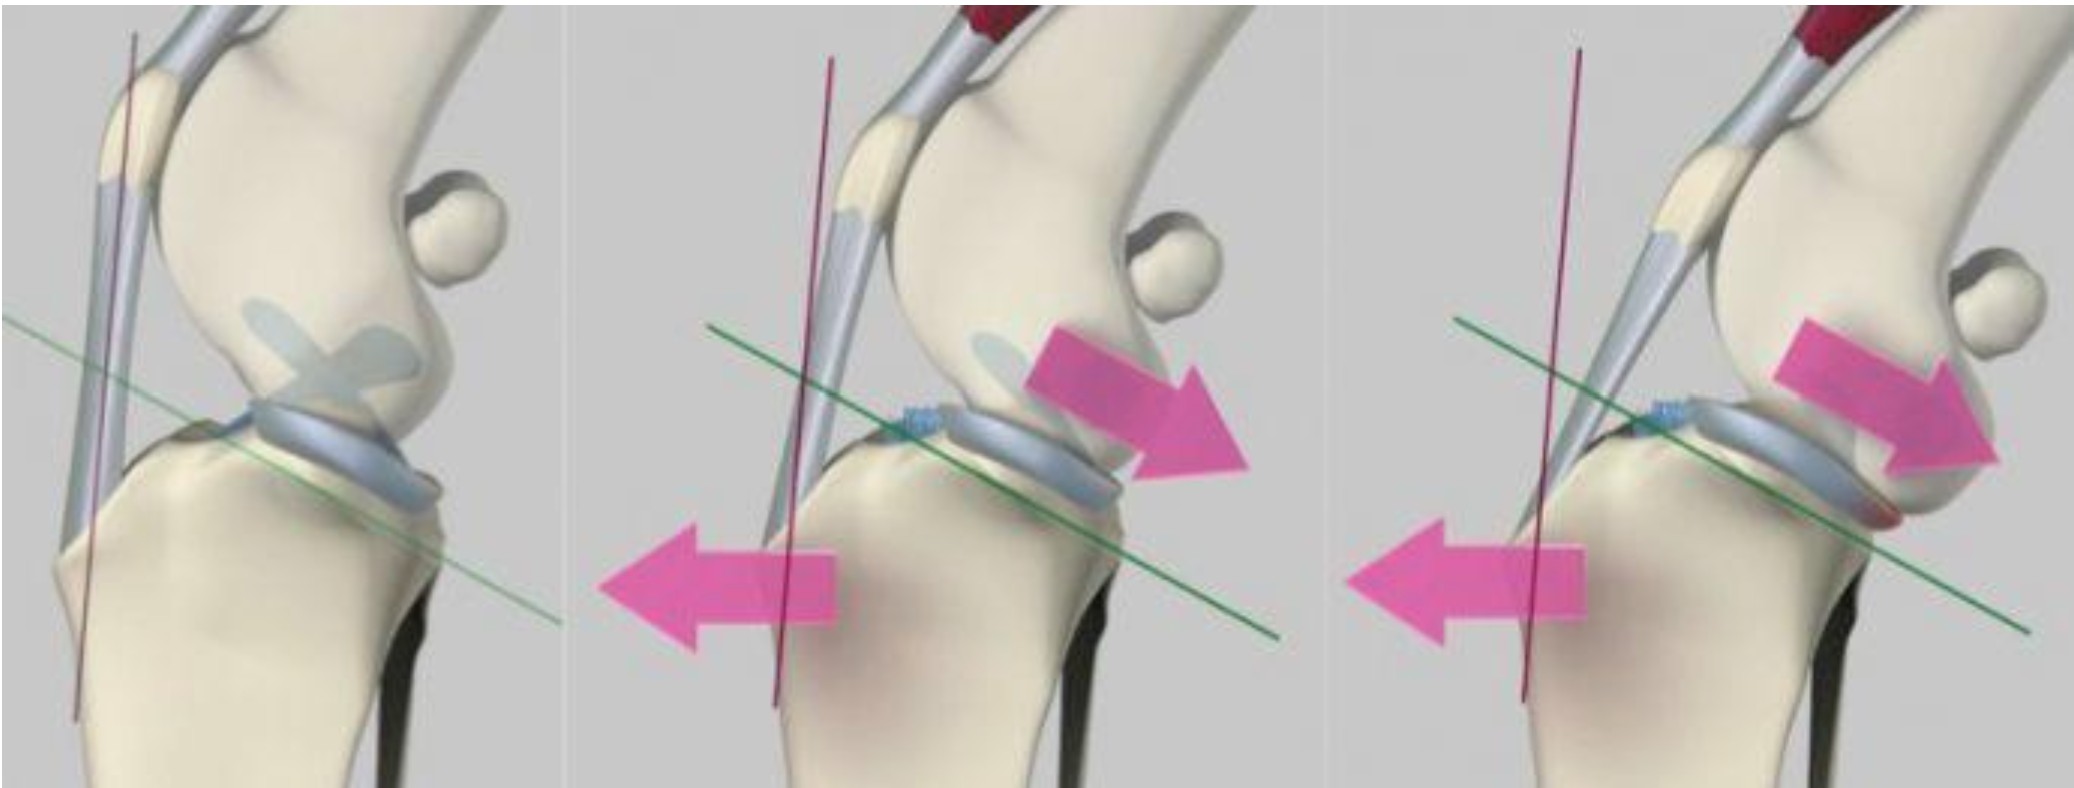

Cruciate ligament disease occurs due to the anatomy of the stifle joint (knee) in dogs. The main function of the cruciate ligament in dogs is to prevent sliding between the tibia bone (shin) and femur bone (thigh). In a normal dog’s stifle, the top of the tibia is sloped backward ~25°, which means there is a natural tendency for the femur bone to slide down this slope when a dog bears weight, which pushes the tibia forward (so-called cranial tibial thrust). This sliding motion is prevented by a normal cruciate ligament; however, this means that the ligament is under load with every step that a dog takes and is one of the main contributing factors to the development of cruciate disease. Once the ligament has ruptured this sliding motion is unconstrained which results in instability, inflammation, pain and progression of osteoarthritis. Stifle instability predisposes other structures within the joint to damage, specifically the medial meniscus, which is a cartilage pad that normally functions to distribute load and improve joint congruency.

Following joint inspection, a radial (circular-shaped) osteotomy is performed in the tibia and the bone fragment is rotated to flatten the slope of the tibia to ~5°. This eliminates the sliding movement between the tibia and femur and effectively stabilises the joint. Finally, a bone plate is applied to secure the bone fragments to allow bone healing.